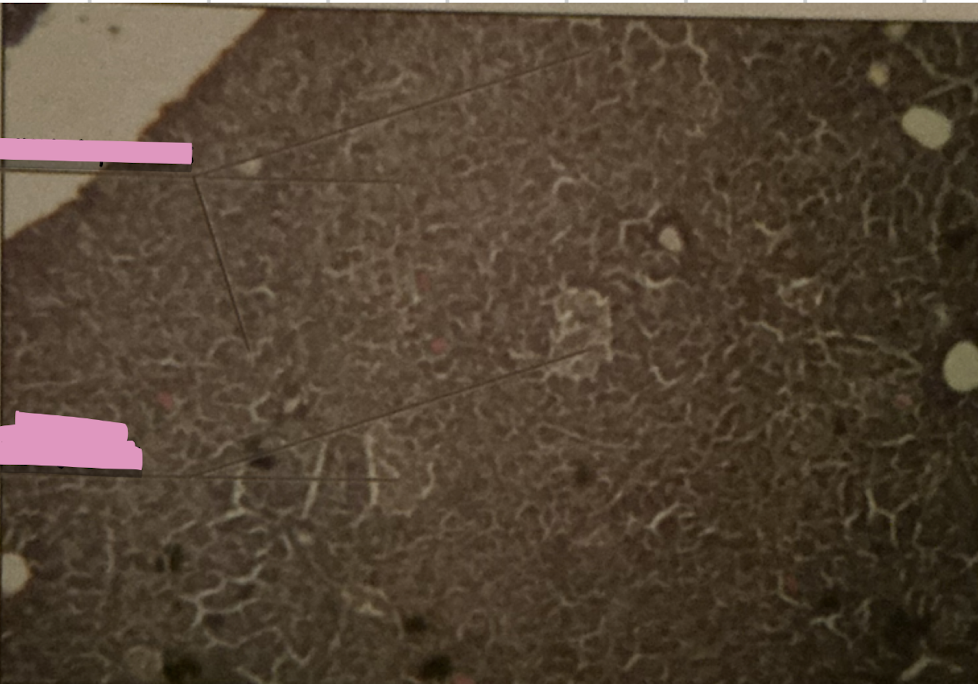

thymus

thymus

where does development of T cells occur?

Hassall’s Corpuscle

___________ sites accumulate dead T cells & involved in development of reg. T cells